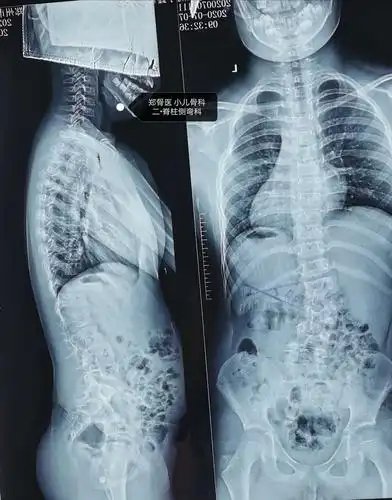

由于脊柱侧弯扭转严重,腰椎变形移位,患者无法配合完成常规的腰穿体位

郑骨医,小儿骨科二脊柱侧弯科短阶段固定治疗脊柱侧弯一例